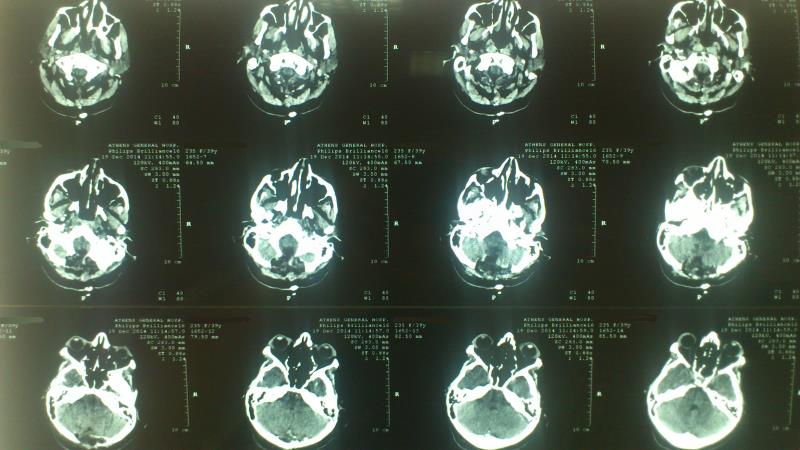

Ασθενής  γυναίκα 49 ετών προσήλθε λόγω υπινιακής κεφαλαλγίας εκλυόμενης και επιδεινούμενης  κατά την επίκυψη και  την άρση βάρους  ( Valsalva maneuvers ) με συνοδό αίσθημα αιμωδιών  άνω και κάτω άκρων. Ο προεγχειρητικός έλεγχος με μαγνητική τομογραφία  του κρανιοσπονδυλικού άξονα ανέδειξε εικόνα συμβατή με Chiari τύπου I : κατάσπαση των παρεγκεφαλιδικών αμυγδαλών 8 mm με κατάληψη- συμφόρηση του ινιακού τρήματος και συνοδό συριγγομυελία καθ’ όλο το μήκος του αυχενοθωρακικου μυελού. Η ασθενής υποβλήθηκε σε υπινιακή κρανιοτομία, αφαίρεση του οπίσθιου τόξου του άτλαντα (Α1) και εκτομή των παρεγκεφαλιδικών αμυγδαλών αποκαθιστώντας την υδροδυναμική του εγκεφαλονωτιαίου υγρού. Πραγματοποιήθηκε πλαστική σκληράς μήνιγγος και δεν επανατοποθετήθηκε ο οστικός κρημνός. Η ασθενής μετεγχειρητικά παρουσίασε  πλήρη ύφεση της κεφαλαλγίας και σταδιακή αποκατάσταση των αιμωδιών. Ο μετεγχειρητικός απεικονιστικός έλεγχος ανέδειξε την αποσυμπίεση στο επίπεδο της κρανιοσπονδυλικής συμβολής και σαφή μείωση των διαστάσεων της συριγγομυελίας.

Μετεγχειρητικός απεικονιστικός έλεγχος